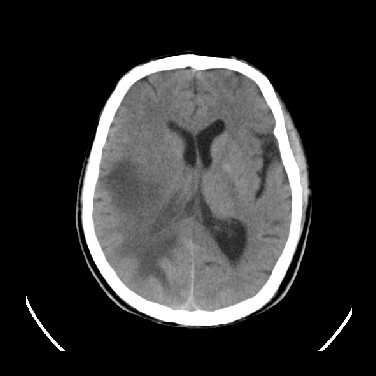

男,45岁,左侧肢体乏力1周。ex:胸片示:两肺团块状、斑片状密度增高影,其内可见小空洞。支纤镜、经皮肺穿示:干酪样物。

结合病史考虑结核性脑炎脑膜炎,伴脑脓肿形成

考虑结核性脑炎脑膜炎,伴脑脓肿形成。

结合病史考虑结核性脑炎脑膜炎,伴脑脓肿形成,囊变转移瘤不除外